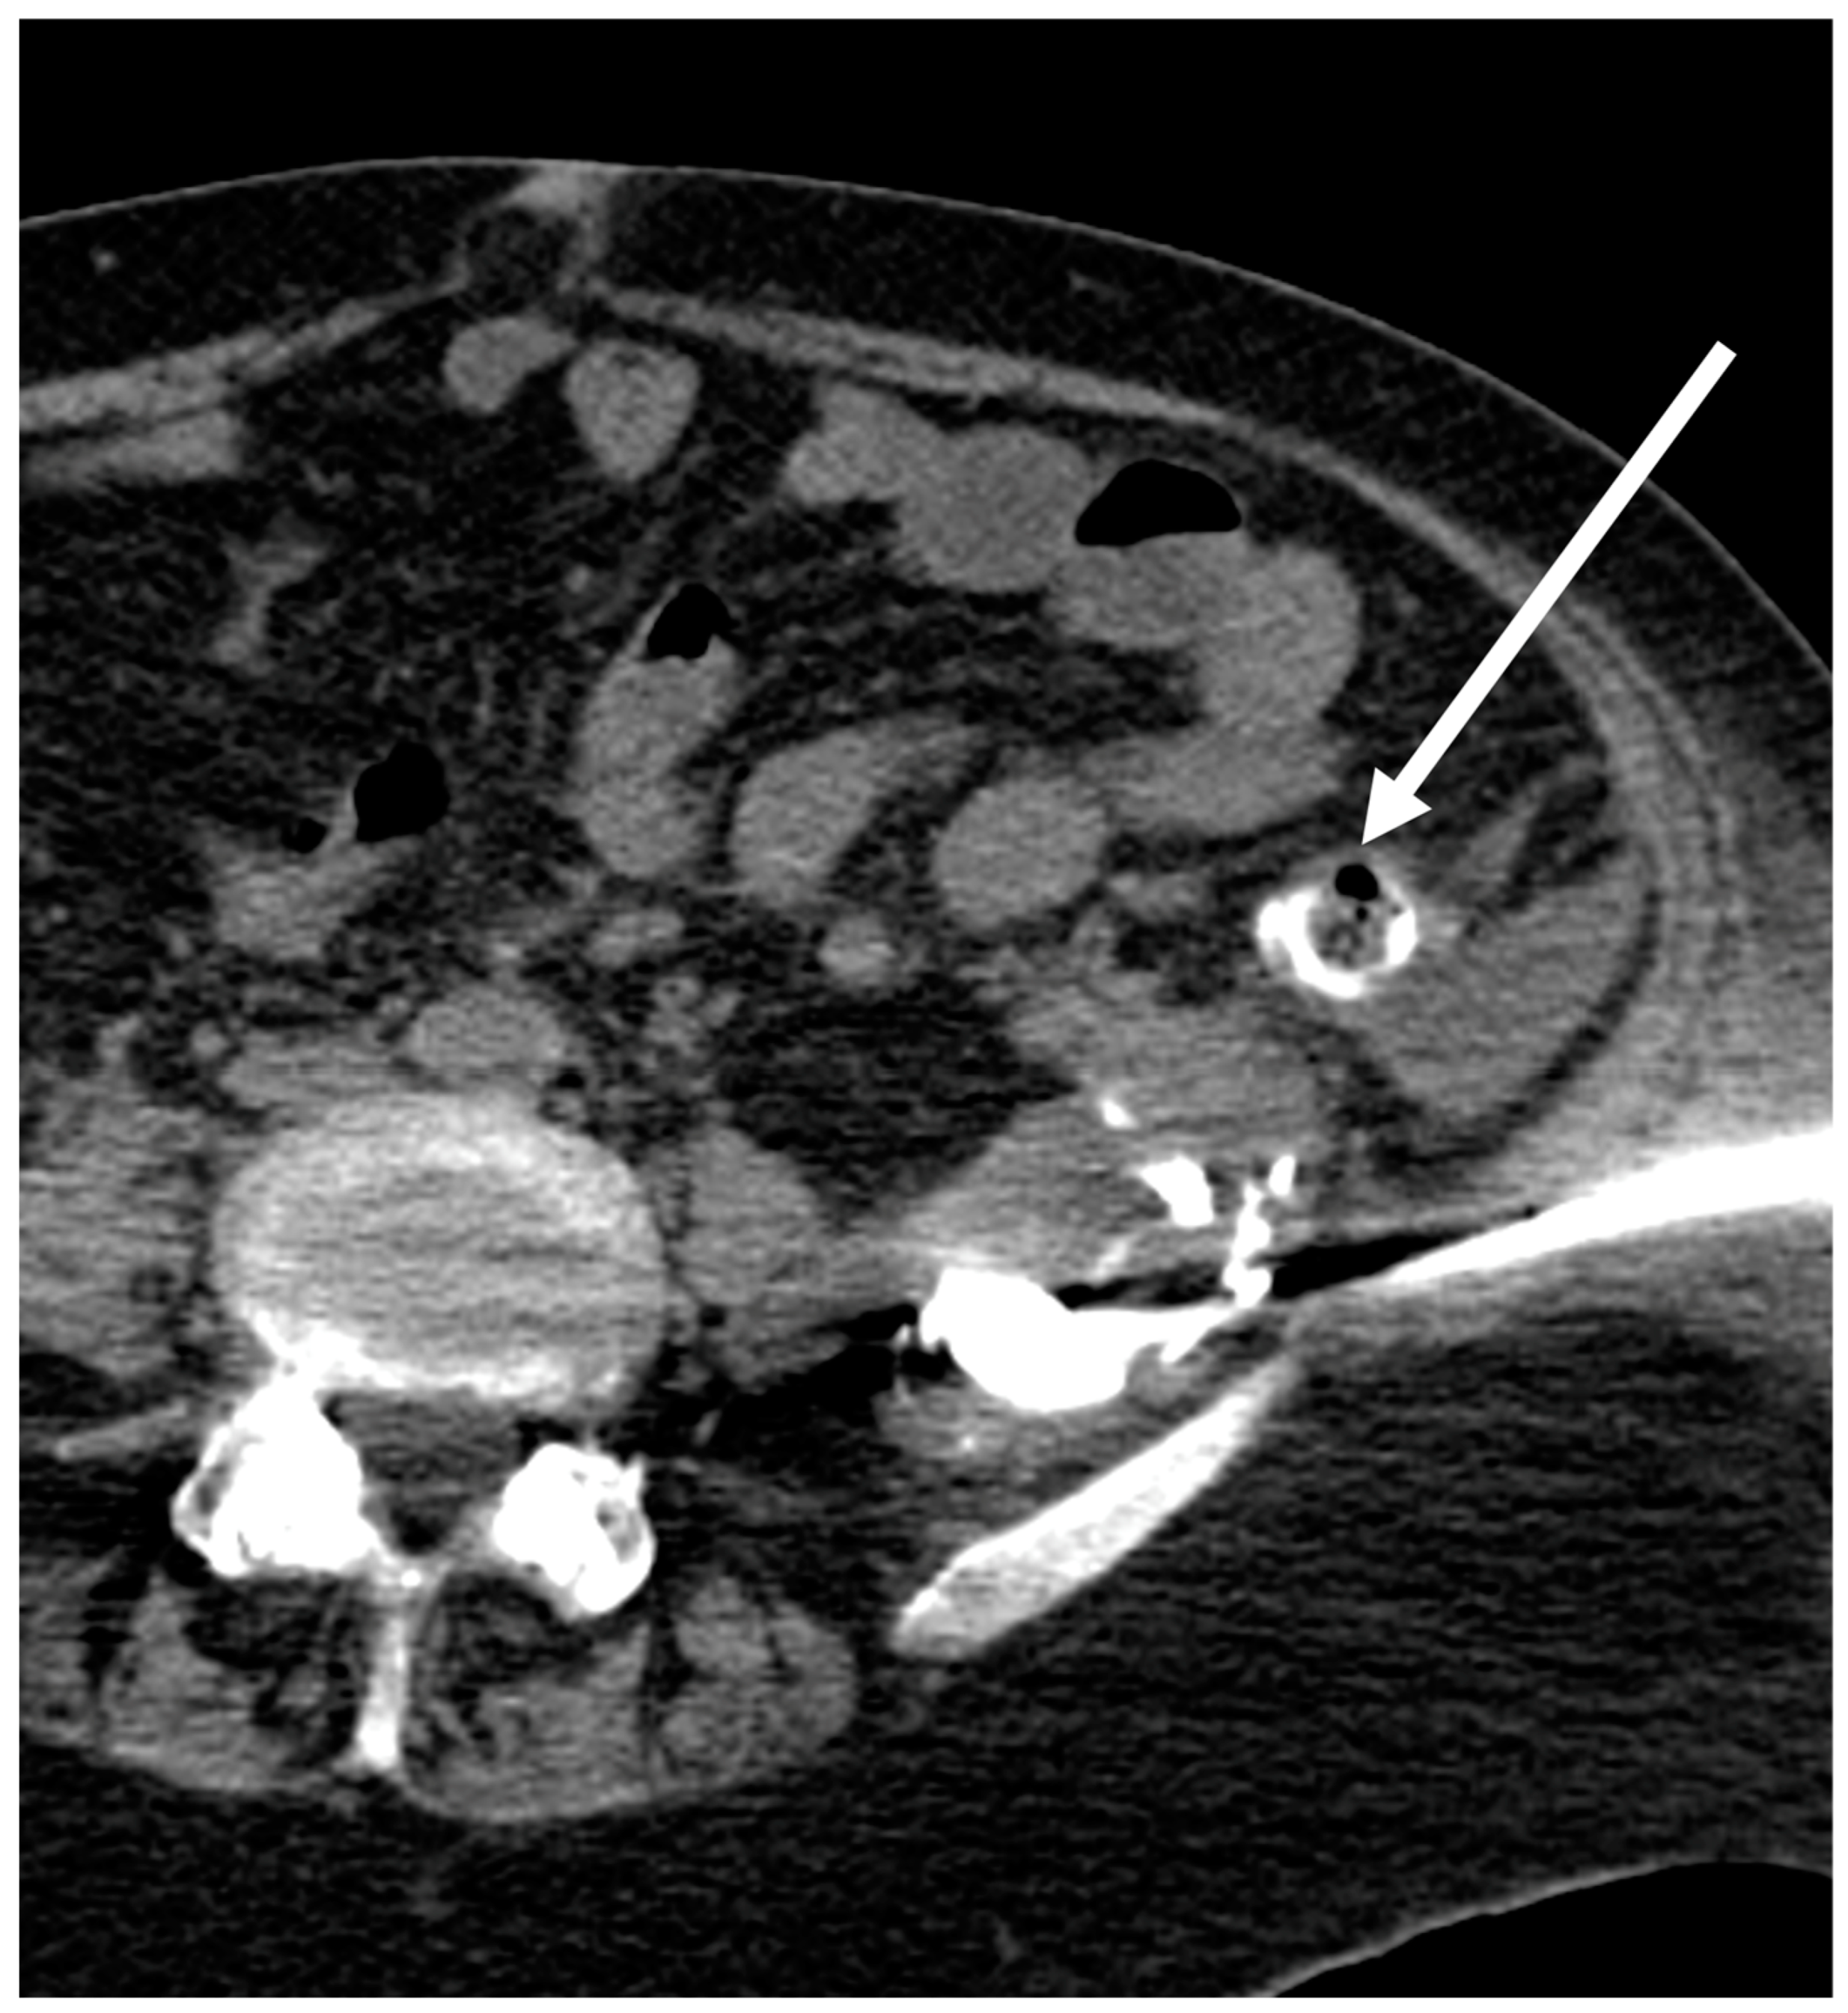

| Misplaced drains | 1 | 0 | 1 |

| Contact with aortic prosthesis | 1 | 0 | 1 |